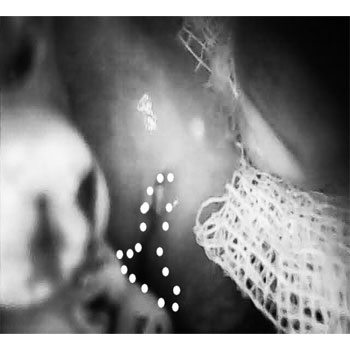

The narrow and mini head of the device can be inserted in to the oral cavity even in restricted mouth opening conditions such as OSMF and Squamous cell carcinomas to allow better visualization even in hidden areas of the oral cavity.

Lesion in Retro molar region with other oral cancer screening devices with larger head and extra oral imaging